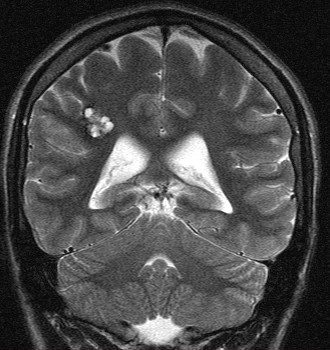

- Краткая информация о пациенте. Пациент К., 19 лет, курсант ВВУЗа. В течение последнего года беспокоили кратковременные приступы дезориентации, что расценено как фокальные приступы с нарушением сознания. За медицинской помощью не обращался до конца августа, когда на фоне полного благополучия появилась интенсивная головная боль. Осмотрен неврологом, рекомендовано выполнение МРТ головного мозга, по данным которого выявлена кавернозная мальформация правой теменной доли с признаками подострого кровоизлияния. Для дальнейшего лечения и обследования госпитализирован в клинику нейрохирургии ВМедА. По данным МРТ головного мозга от 06.09.2021 г.: определяется кавернозная мальформация правой теменной доли, прилежащая к зоне центральных извилин с признаками подострого кровоизлияния общими размерами 2.0х1.5х1.7 см.

МРТ головного мозга: кавернозная мальформация правой теменной доли с признаками кровоизлияния